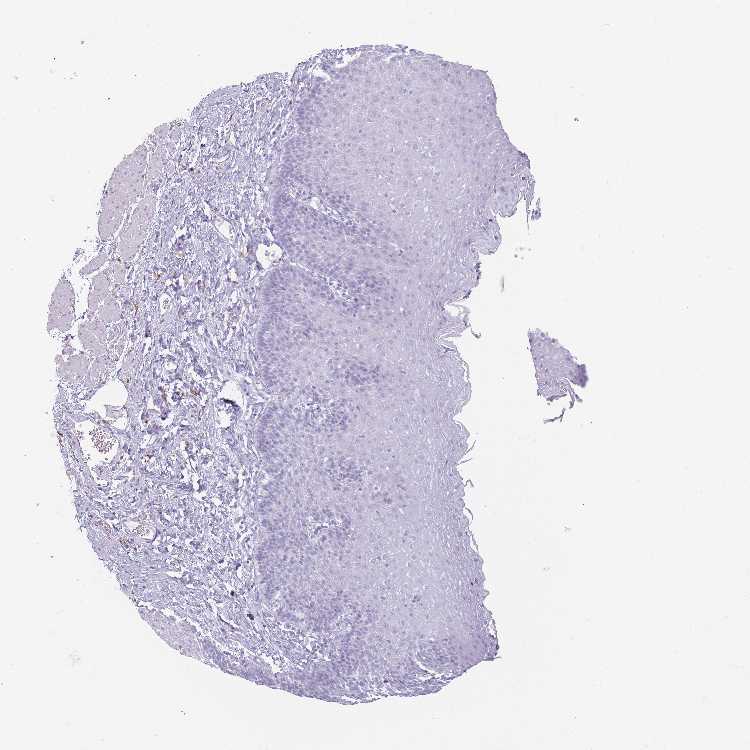

ESOPHAGUS - Antibody stainingi

Antibody staining in the annotated cell types in the current human tissue is reported as not detected, low, medium, or high, based on conventional immunohistochemistry profiling in selected tissues. This score is based on the combination of the staining intensity and fraction of stained cells.

Each image is clickable and will lead to virtual microscopy that enables deeper exploration of all samples and also displays staining intensity scores, fraction scores and subcellular localization as well as patient and tissue information for each sample.

Antibody HPA047917

Squamous epithelial cells Not detected